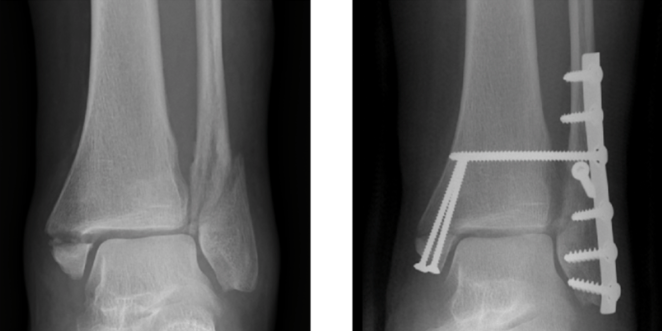

New Addition: Ankle Open Reduction and Internal Fixation

We are pleased to announce that we have added a new surgery to the Perioperative Pain Management Pathway. You can now review the pain management best practices for an ankle open reduction and internal fixation, over in our collection of orthopedic procedures.